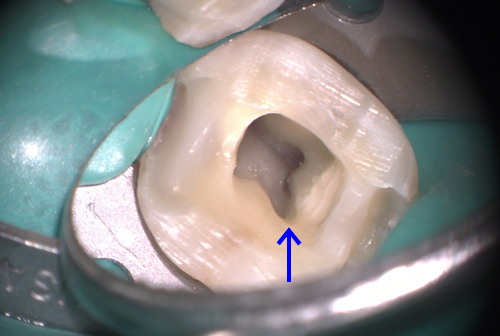

印象の際に歯肉の下の部分を確実に型取りするために行うのが圧排という作業です。下のイラストの青い部分が圧排コードです。これを入れてこの部分を広げて印象材を注入します。詳しくはこの辺を参照してください。実は印象材の違いによる寸法精度の差は大きくないのですが、寒天印象材は簡単に千切れるので上の写真のような印象は不可能なのです。

こういったところでもマイクロスコープは活躍します。動画はダブルコードテクニックというのですが、細い糸を一本入れてその後太い糸を入れ、印象材を流すときに太い糸だけ取り除きます。